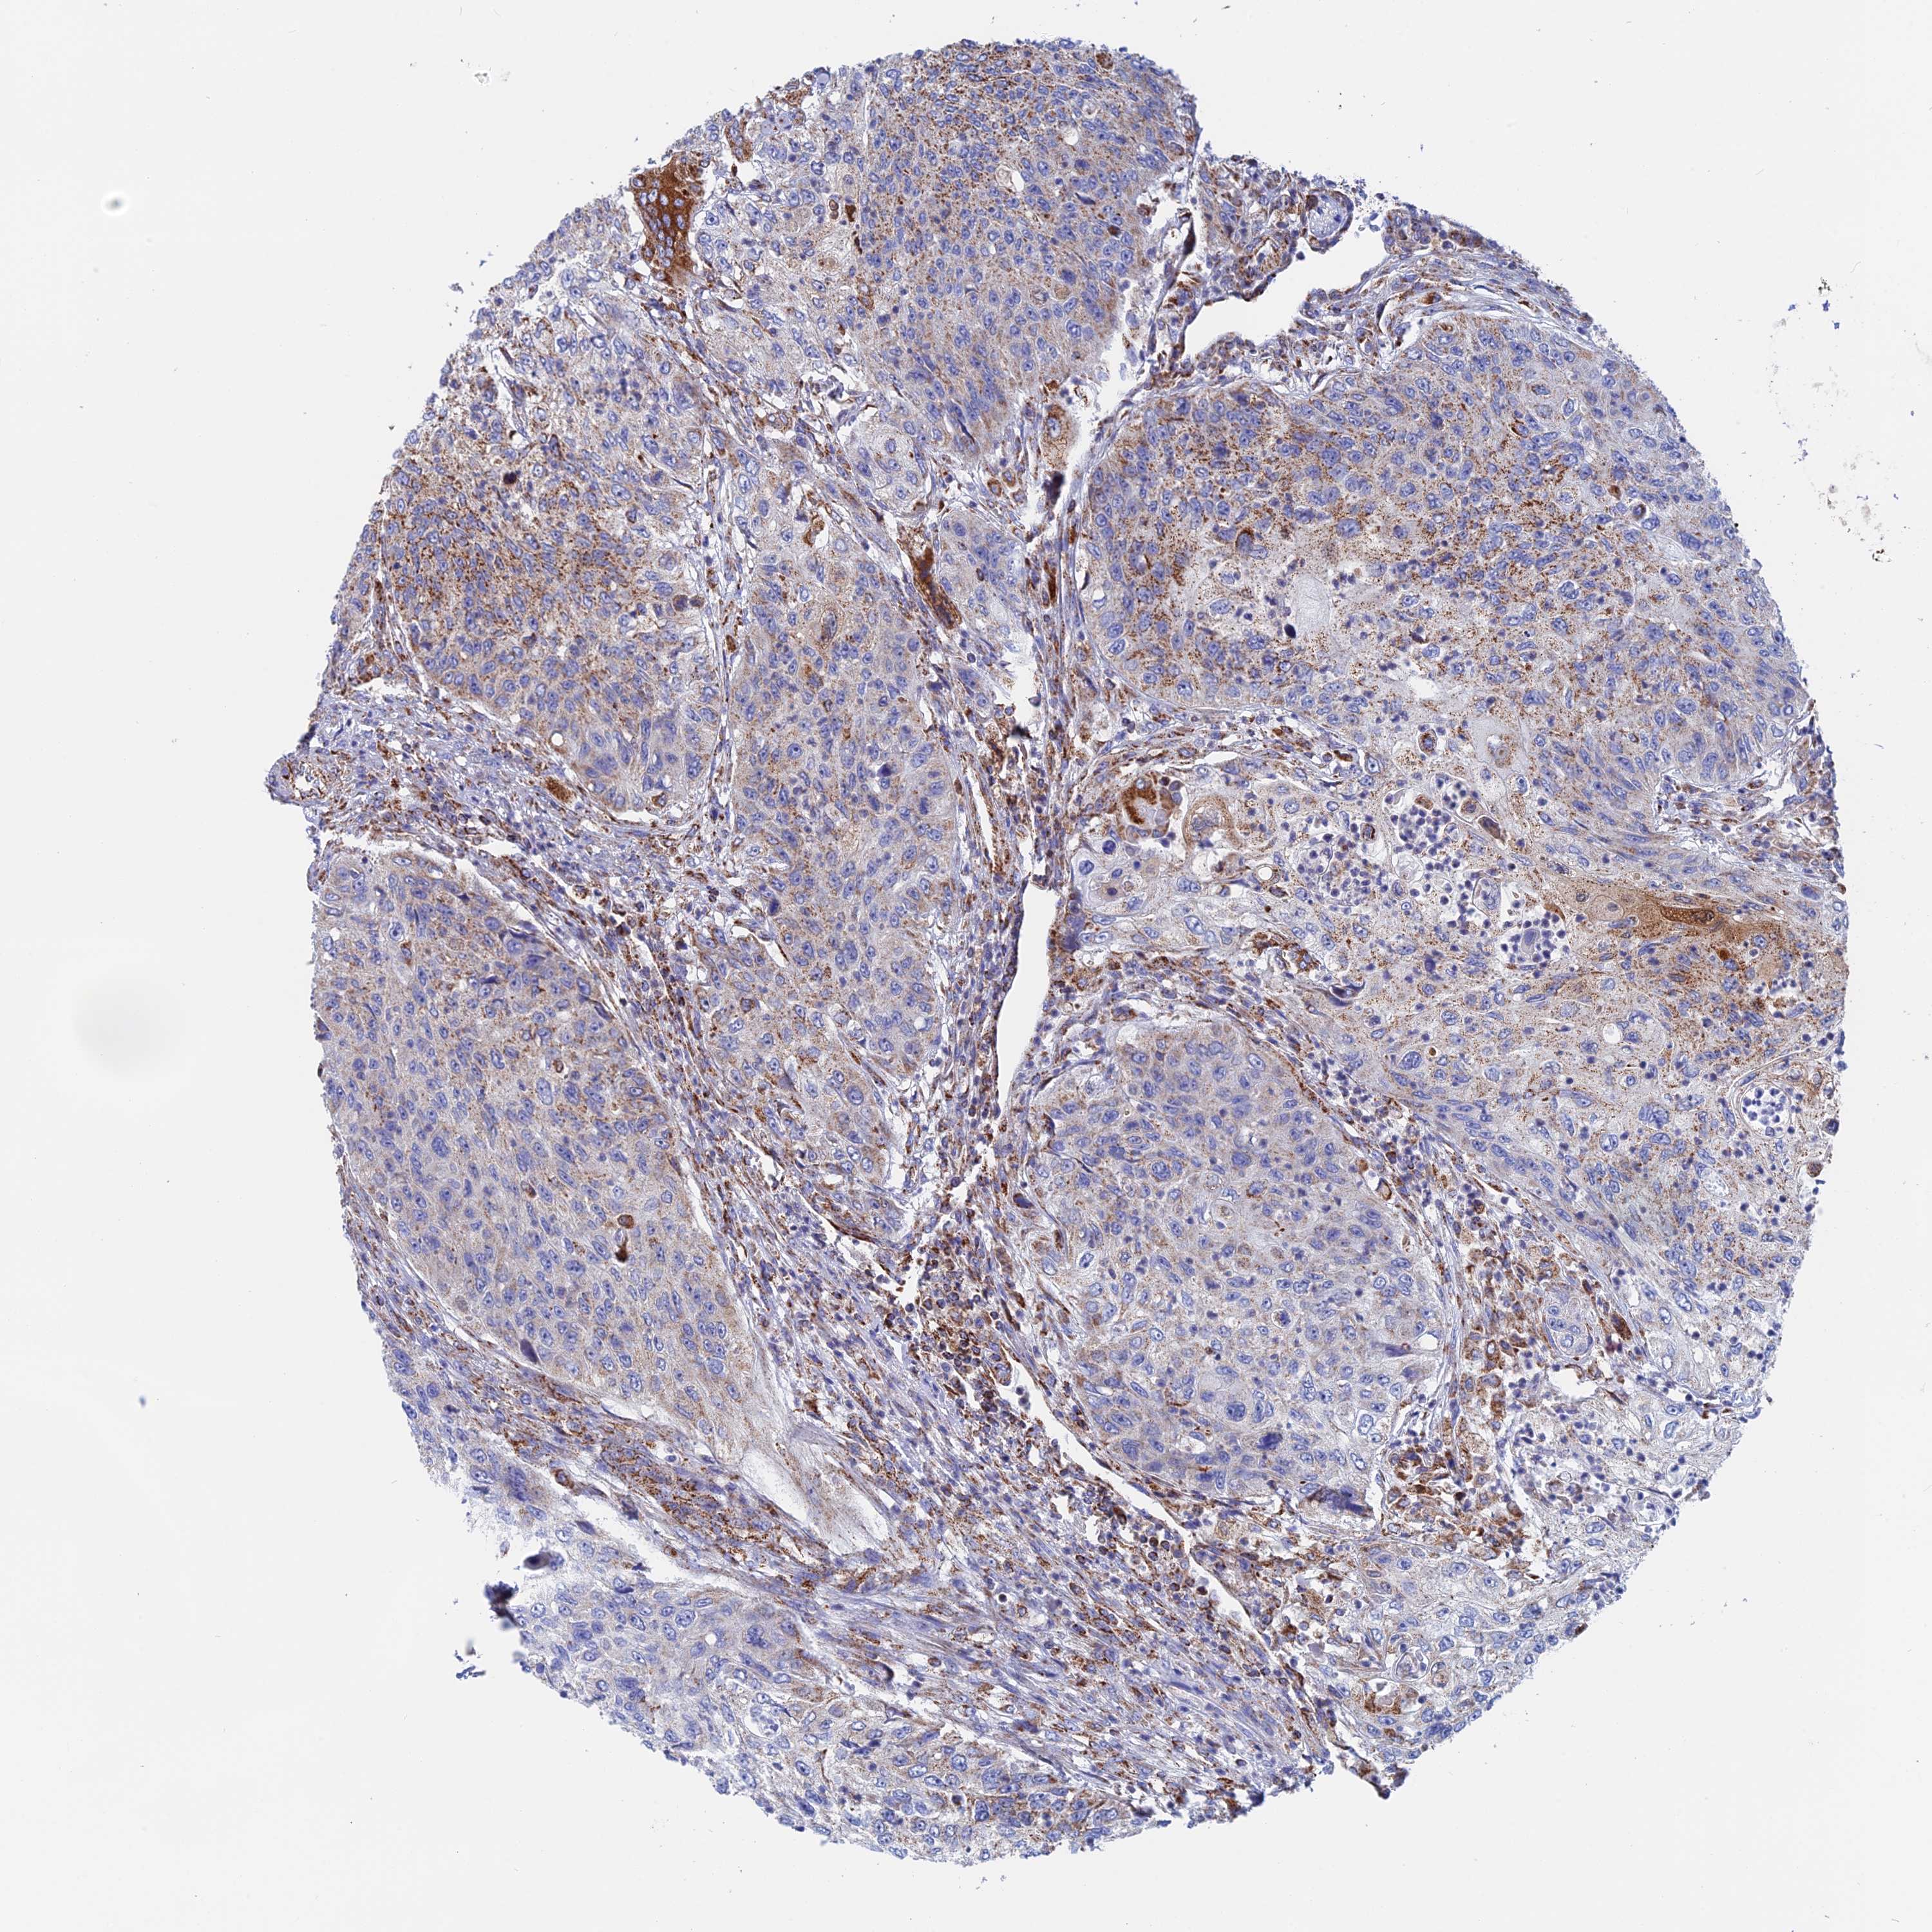

UROTHELIAL CANCER - Protein expressioni

A mouse-over function shows sample information and annotation data. Click on an image to view it in a full screen mode. Samples can be filtered based on level of antibody staining by selecting one or several of the following categories: high, medium, low and not detected. The assay and annotation is described here.

Antibody stainingi

Antibody staining in the annotated cell types in the current human tissue is reported as not detected, low, medium, or high, based on conventional immunohistochemistry profiling in selected tissues. This score is based on the combination of the staining intensity and fraction of stained cells.

Each image is clickable and will lead to virtual microscopy that enables deeper exploration of all samples and also displays staining intensity scores, fraction scores and subcellular localization as well as patient and tissue information for each sample.

Antibody HPA042629

Antibody HPA042838

Staining

High

Medium

Low

Not detected

Intensity

Strong

Moderate

Weak

Negative

Quantity

>75%

75%-25%

<25%

None

Location

Nuclear

Cytoplasmic/membranous

Cytoplasmic/membranous,nuclear

Urothelial carcinoma, High grade